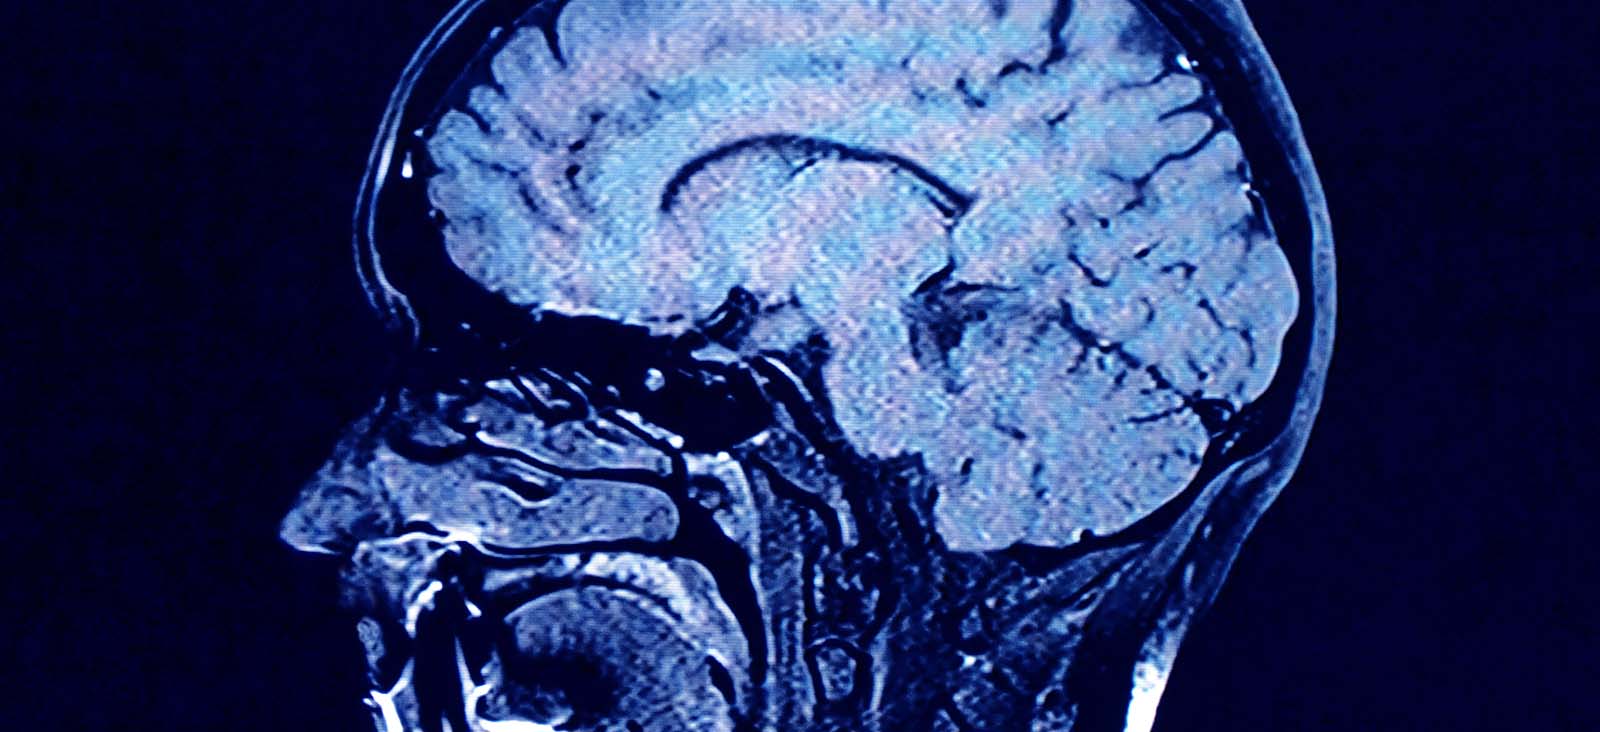

UT Southwestern Medical Center offers specialized neuropsychological assessment of people with known or suspected neurological disorders or brain injuries that result in cognitive, personality, or behavioral problems. These problems can include difficulties with memory, attention, executive functioning, depression, anxiety, or mood instability.